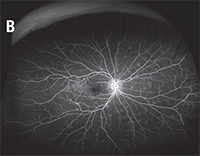

| Figure 2. Optos widefield images of a patient with multiple evanescent white dot syndrome. The color fundus photo demonstrates multiple focal gray/white lesions in the posterior pole and, more extensively, in the periphery (A). Similar findings are more apparent on fluorescein angiography with notable late-phase staining (B). | |

WF imaging has been helpful to identify and monitor the extent of disease in uveitic patients, particularly those with peripheral lesions or retinal vasculitis, has been helpful. In multiple evanescent white dot syndrome, multi-modality imaging makes the extent of peripheral pathology more evident (Figure 2).A small, consecutive case series of four patients with retinal vasculitis that compared conventional FA based on ETDRS protocols to WF FA found that conventional FA could not visualize the full extent of vasculitis and capillary occlusion in any fields.5 While the diagnosis of retinal vasculitis was established, the underlying etiology was not determined in all but one patient diagnosed with Vogt-Koyanagi-Harada disease. Notably, the study found conventional FA would not have detected the posterior extent of vasculitis in two cases.